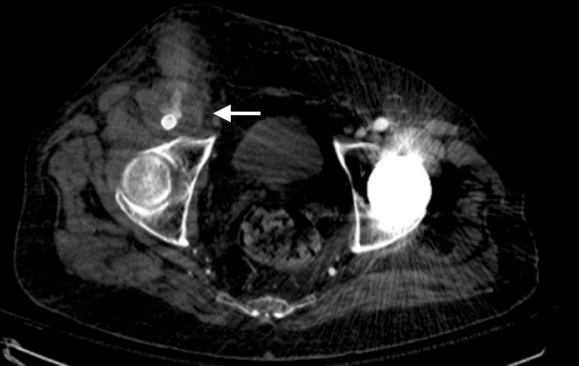

On physical examination, the patient was septic, lethargic with grossly infected groin (image above). A CT scan with contrast was performed which showed active extravasation with stranding around the femoral vessels (below).